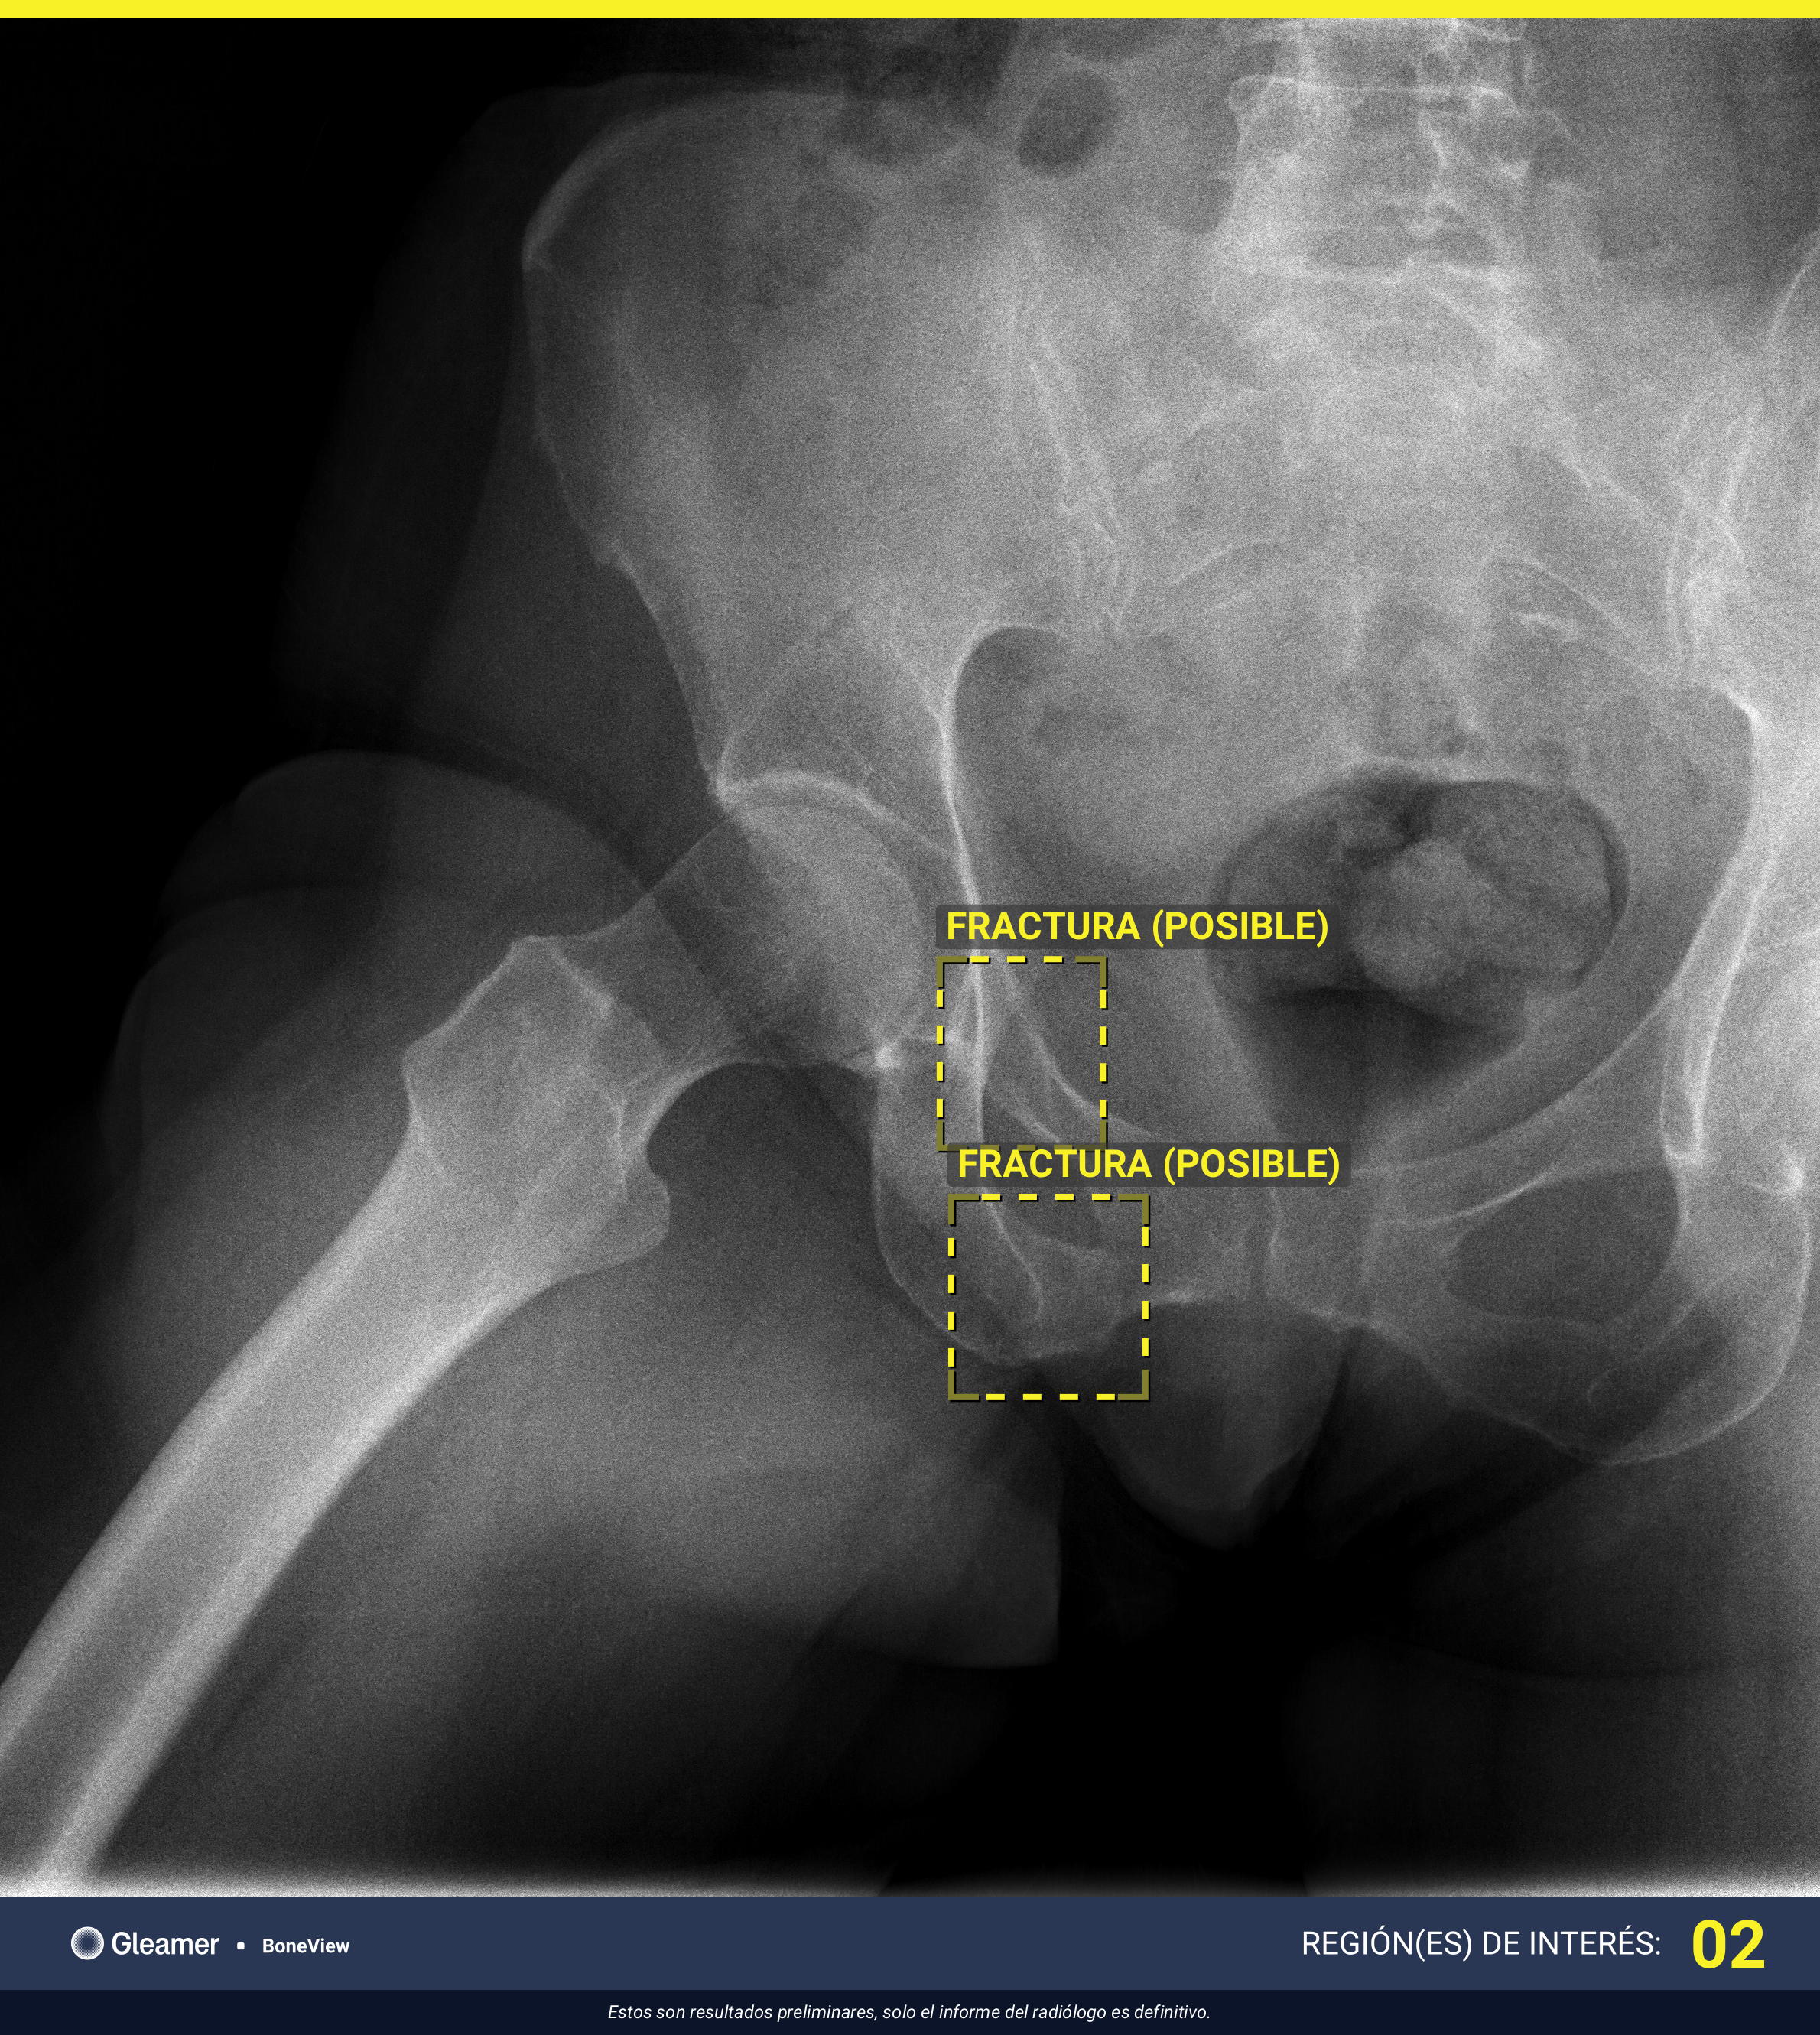

902 DOUBT